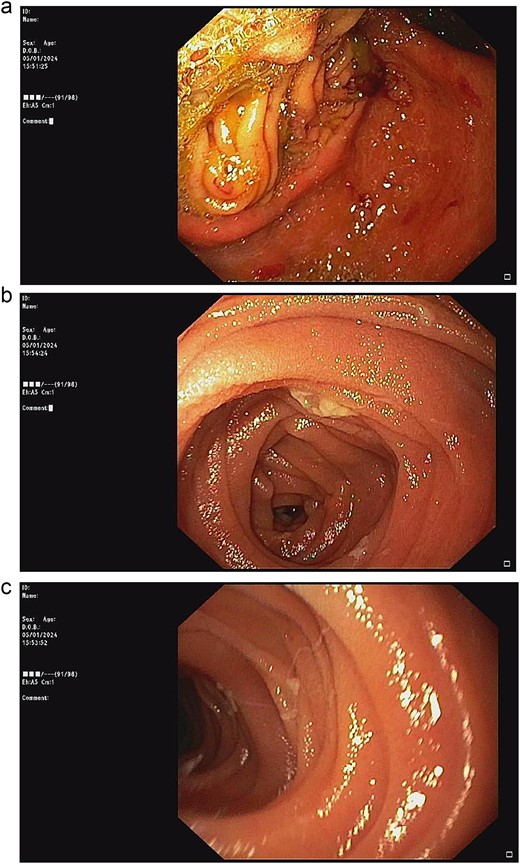

After 2 weeks of conservative treatment, the content from afferent limb decreased to 100–200 ml per day. Subsequently abdominal radiography showed collapsed stomach and normal bowel gas pattern. Oral contrast study revealed that contrast passed through small bowel and large bowel in 6 hours (Fig. 4). The patient was able to resume an oral diet and discharge at hospital admission Day 25th. On 3-mo follow-up, the patient could have solid food without any symptom.

Two weeks of conservative treatment: (a) abdominal plain film, (b) oral contrast study.